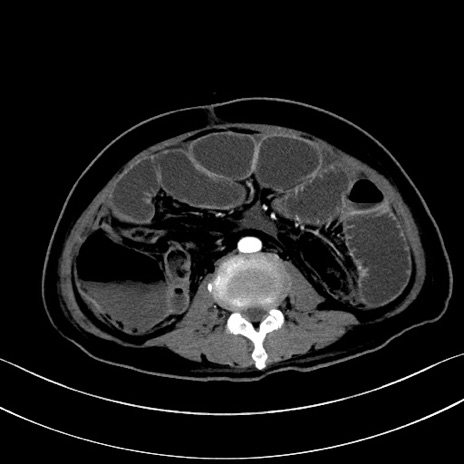

症例28(横断像)

【症例】60歳代男性

【主訴】嘔吐

【現病歴】胃癌にて胃全摘後。食思不振が悪化し、夜中に嘔吐することがある。

【既往歴】胃癌、胃全摘、脾摘、胆摘後

【データ】WBC 5900、CRP 10.56